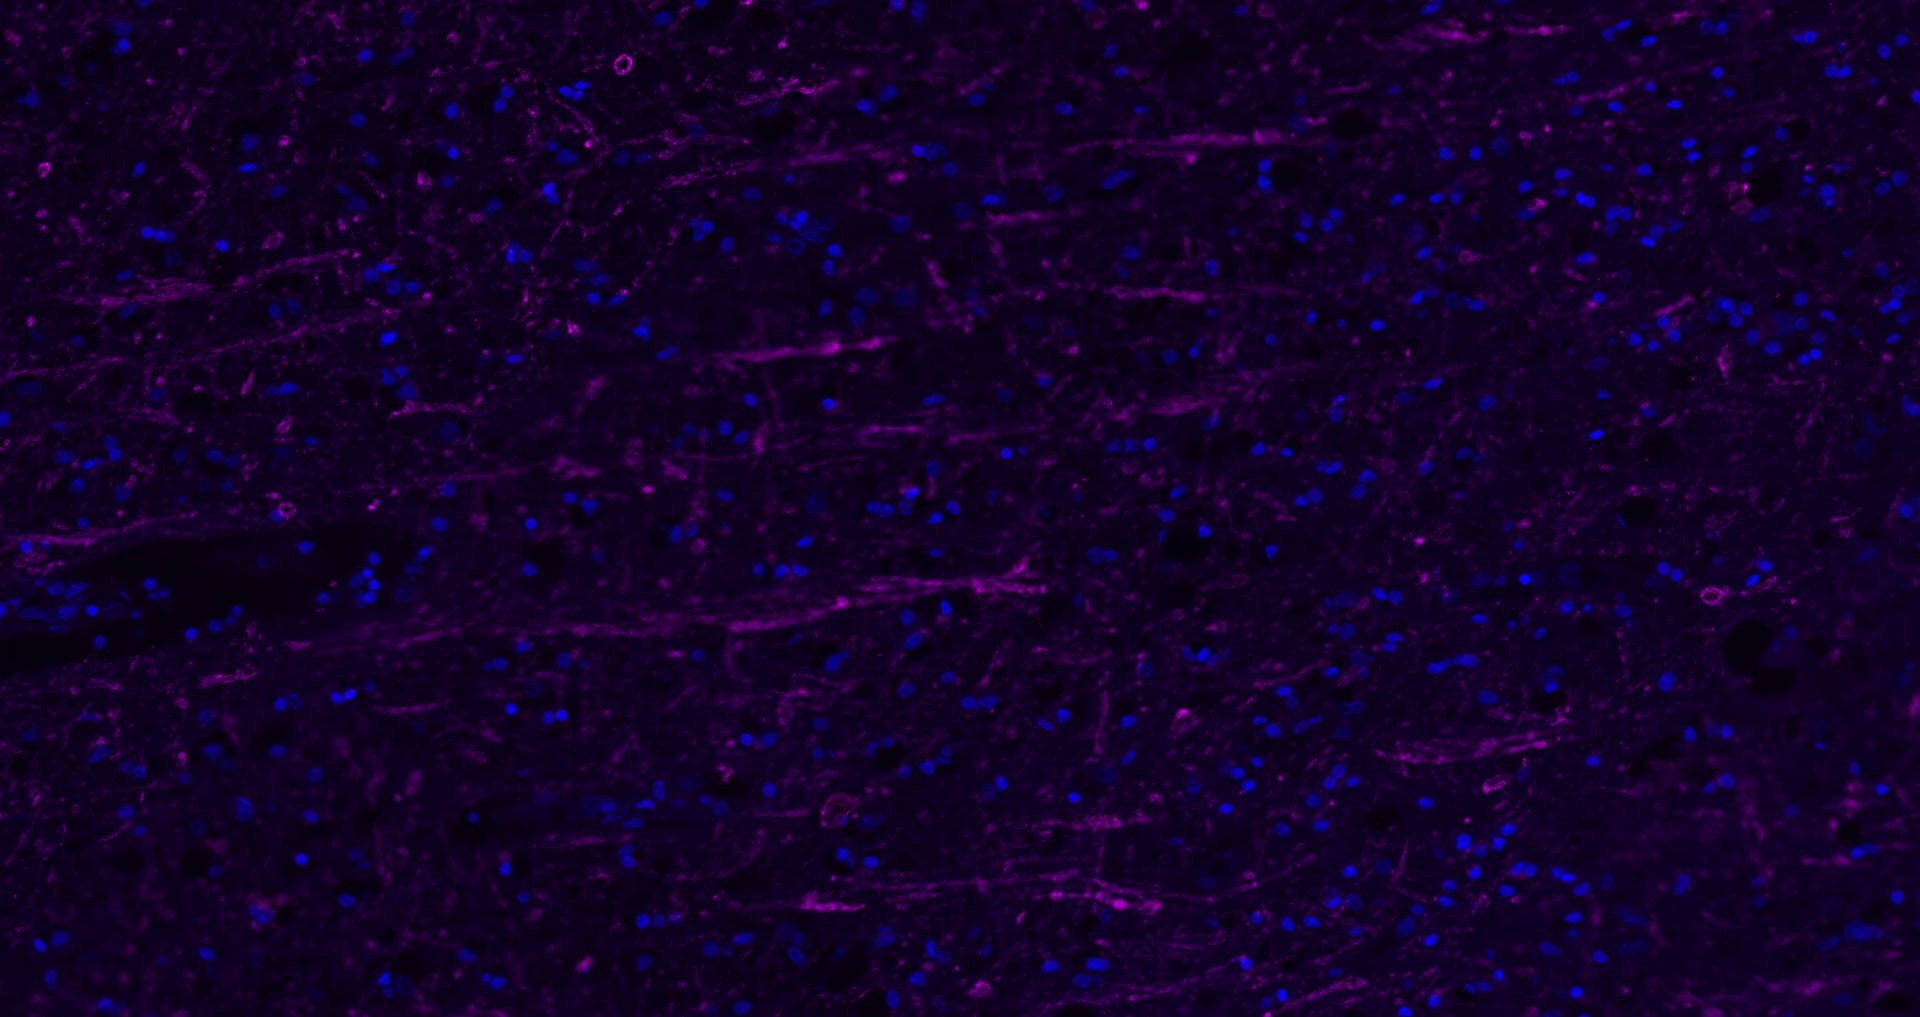

11. Paraformaldehyde-fixed, paraffin embedded Mouse Cerebellum; Antigen retrieval by boiling in sodium citrate buffer (pH6.0) for 15 min; The section was incubated with MBP Polyclonal Antibody, Unconjugated (TMAB-01110) at 1:1500 overnight at 4°C, followed by conjugation to the secondary antibody and DAB staining.

12. Paraformaldehyde-fixed, paraffin embedded Rat Cerebellum; Antigen retrieval by boiling in sodium citrate buffer (pH6.0) for 15 min; The section was incubated with MBP Polyclonal Antibody, Unconjugated (TMAB-01110) at 1:1500 overnight at 4°C, followed by conjugation to the secondary antibody and DAB staining.

13. Paraformaldehyde-fixed, paraffin embedded Human Cerebellum; Antigen retrieval by boiling in sodium citrate buffer (pH6.0) for 15 min; The section was incubated with MBP Polyclonal Antibody, Unconjugated (TMAB-01110) at 1:1500 overnight at 4°C, followed by conjugation to the secondary antibody and DAB staining.

14. Paraformaldehyde-fixed, paraffin embedded Human Cerebrum; Antigen retrieval by boiling in sodium citrate buffer (pH6.0) for 15 min; The section was incubated with MBP Polyclonal Antibody, Unconjugated (TMAB-01110) at 1:1500 overnight at 4°C, followed by conjugation to the secondary antibody and DAB staining.